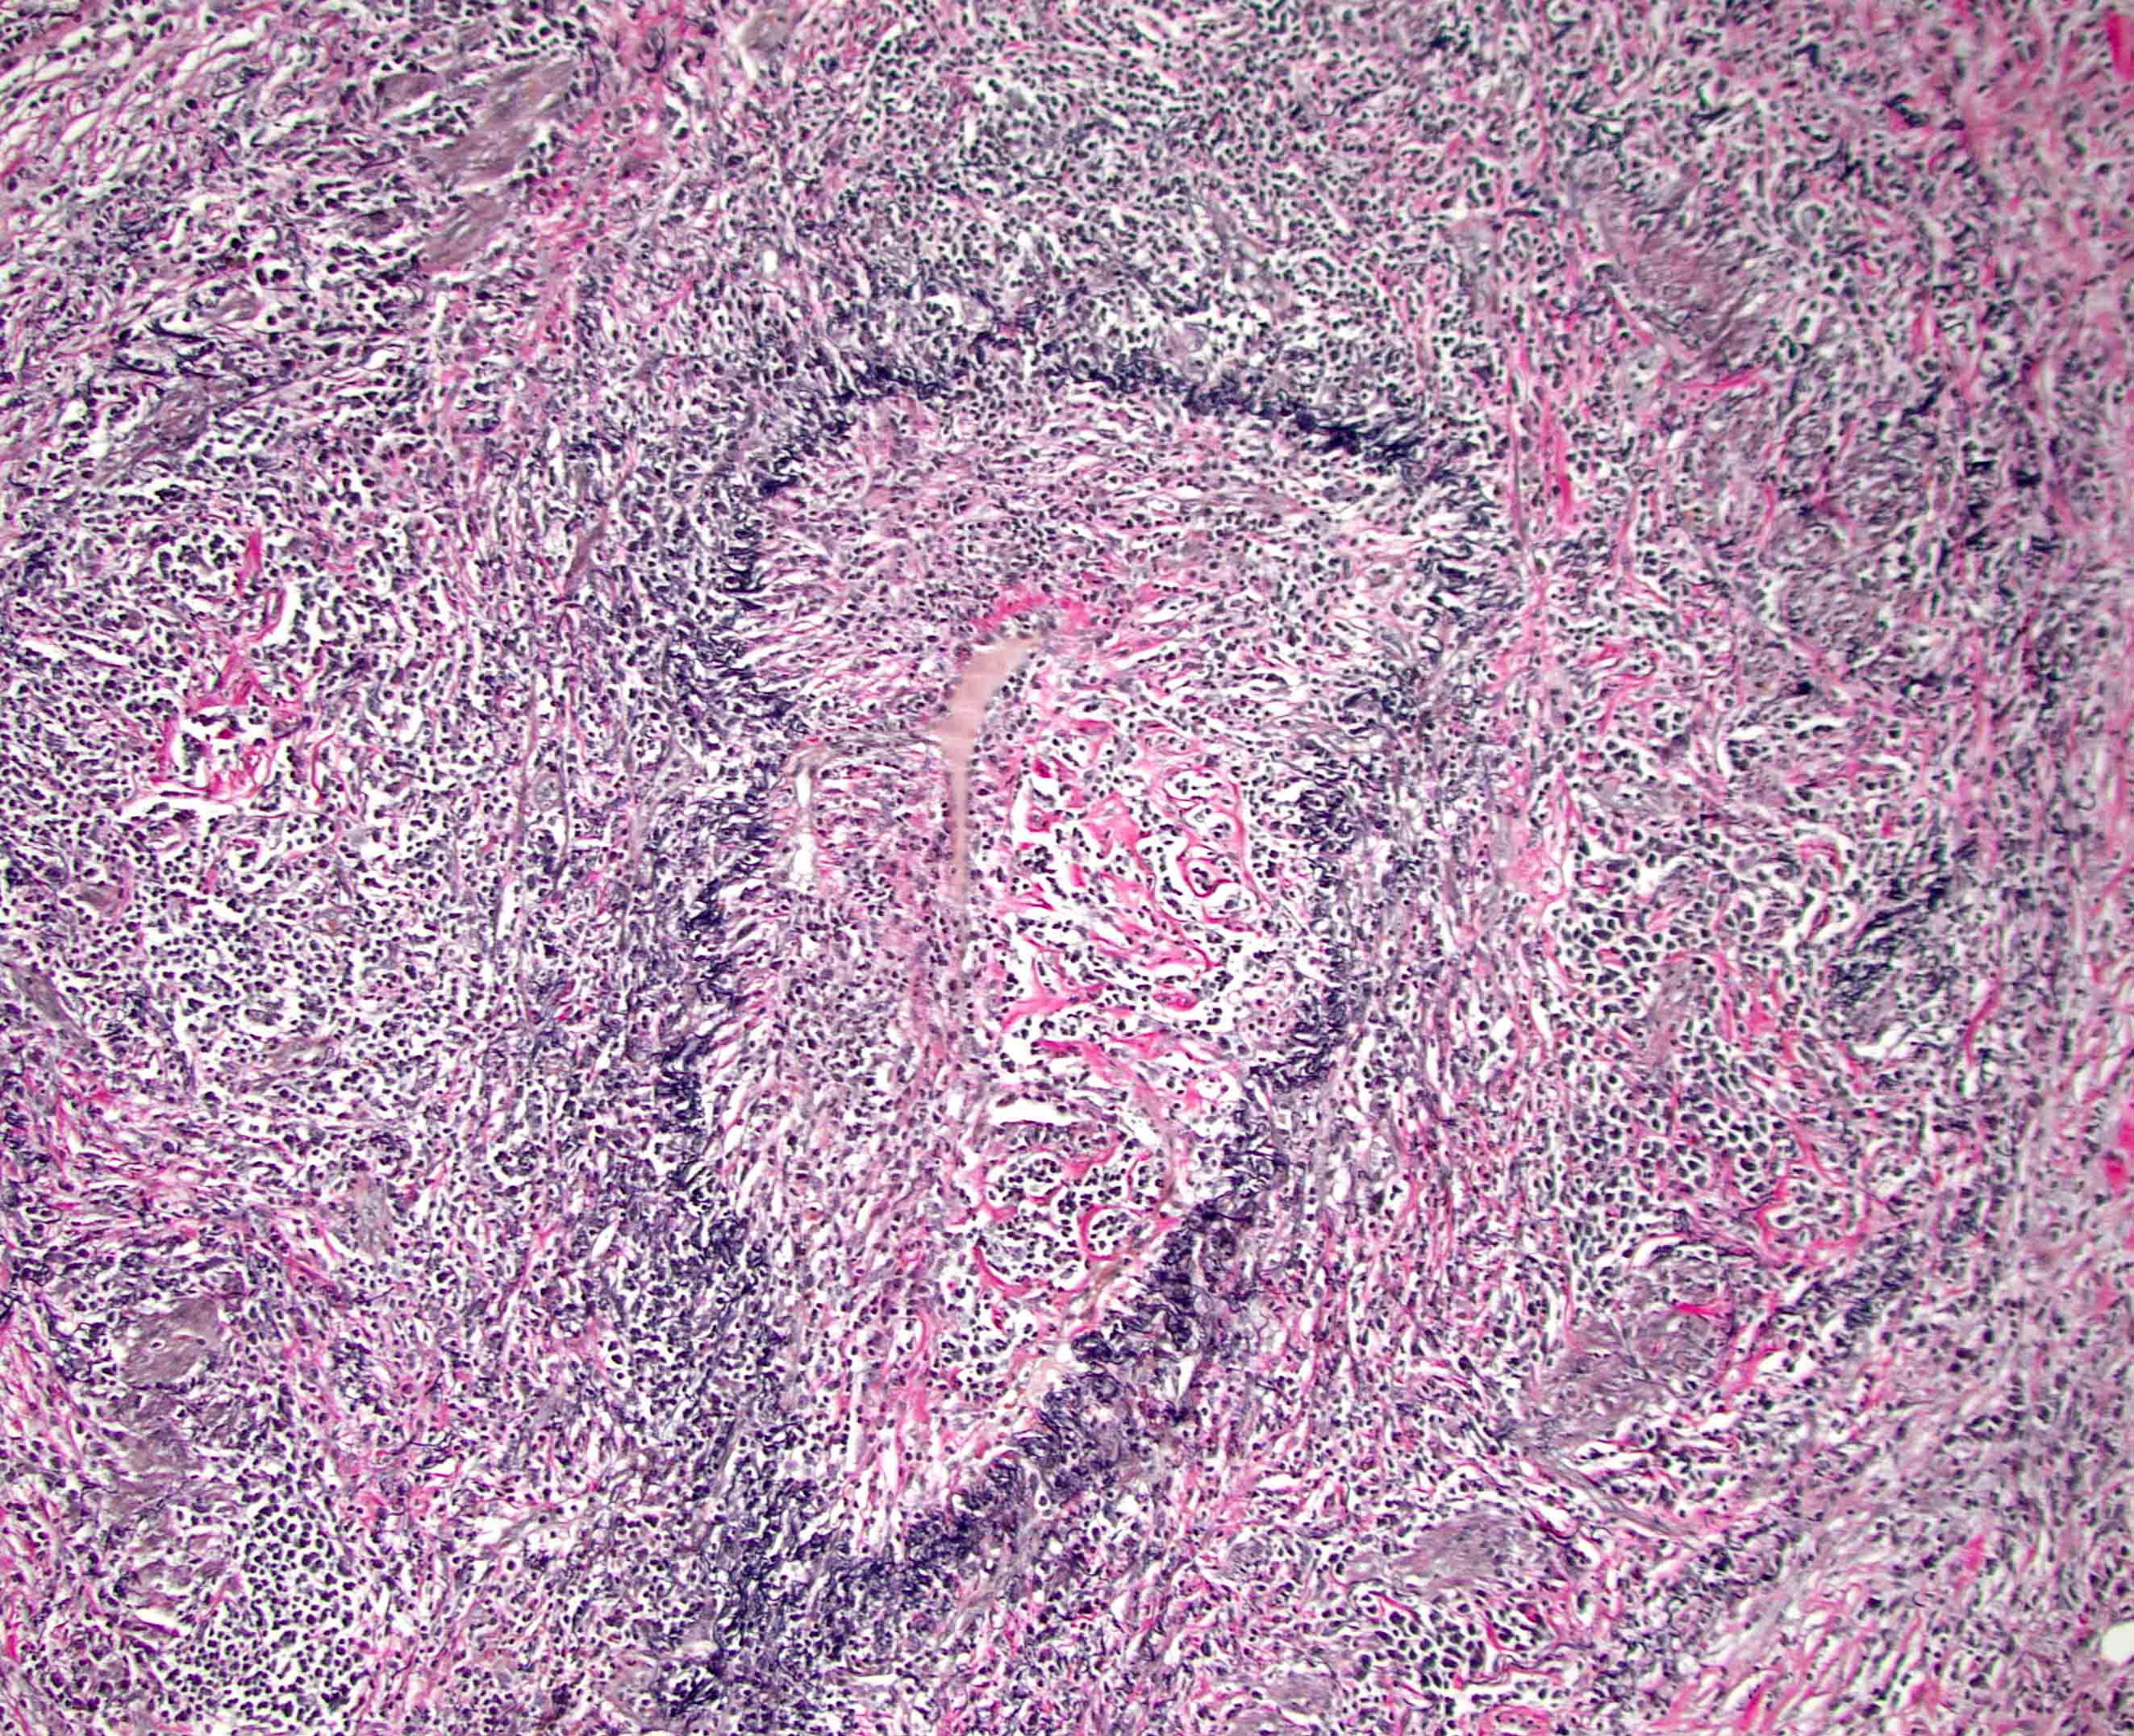

Microscopic (histologic) description

- Characteristic findings (at least 3 for level 1 criteria) (Pancreas 2011;40:352)

- Periductal lymphoplasmacytic infiltrate without granulocytic infiltration

- Obliterative phlebitis

- Storiform fibrosis

- Abundant (> 10 cells/high power field) IgG4 positive plasma cells

- Biopsy showing some but not all of the above features can be used as supportive evidence for the diagnosis of autoimmune pancreatitis (Pancreas 2011;40:352)

- Inflammation is localized within the pancreatic parenchyma and is centered around / within medium to large interlobular ducts, which causes shrinkage of the ductal lumen (Pathologica 2020;112:197)

- Inflammation can also be seen between the pancreatic parenchyma and peripancreatic adipose tissue (Pathologica 2020;112:197)

- Inflammation of the venous wall can progress to obliterative phlebitis with fibrosis of the lumen (Pathologica 2020;112:197)

- As the inflammation progresses, fibrosis becomes more diffuse, assuming a whorled or storiform pattern (Pathologica 2020;112:197)

- Perineural inflammation can also be present (Pathologica 2020;112:197)

Microscopic (histologic) images